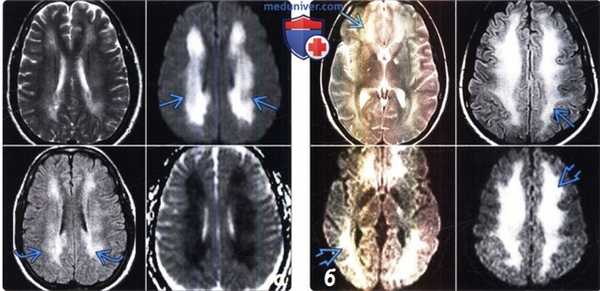

(а) У мужчины 57 лет после курения героина методом «погони за драконом» остро развилась лейкоэнцефалопатия. По данным МРТ определяется диффузное повышение интенсивности сигнала на T2-BИ/FLAIR-изображении (слева), и острое ограничение диффузии (справа).

(б) По данным МРТ у женщины 32 лет с передозировкой метадоном отмечается симметричное повышение интенсивности сигнала на T2-BИ/FIAIR-изображении в сочетании с острым ограничением диффузии на ДВИ.